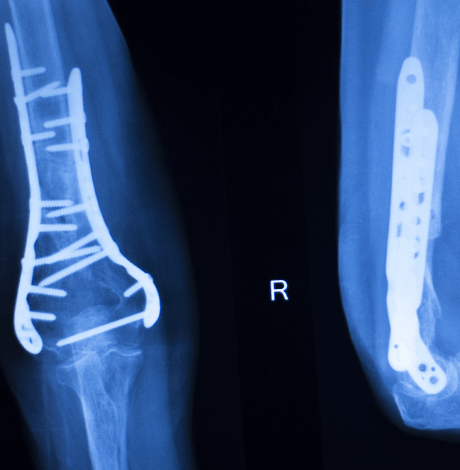

Titanium Plate Surgery (ORIF) at Yashoda hospitals.

Titanium plates are frequently used in surgeries such as open reduction & internal fixation (ORIF) to stabilize bones and encourage the healing process after fractures. Fractures can occur at any age due to trauma from falls, car accidents, or sports injuries, and titanium plates provide durable support to help bones heal correctly. Additionally, certain medical conditions or repetitive activities, like running, can increase the risk of fractures, making titanium plate fixation a valuable solution for restoring bone stability and function.

The Department of Orthopedics and Joint Replacements at Yashoda Hospitals works meticulously round the clock with 24/7 trauma and emergency care under the supervision of the best trauma surgeons and orthopedic specialists. With road traffic accidents becoming increasingly common, our department is dedicated to handling critical cases like complex trauma with multiple fractures under the highest level of expertise, with procedures such as open reduction & internal fractures (ORIF).